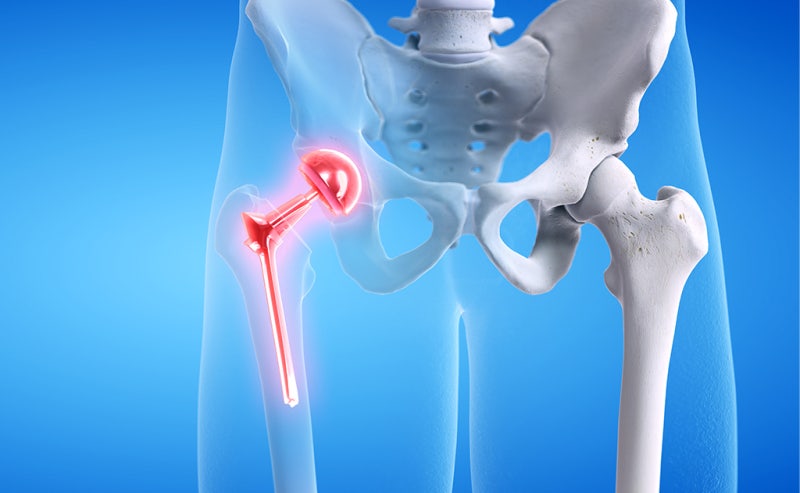

고관절 수술은 많은 사람들에게 필요한 복잡한 수술입니다. 나이가 들면서 또는 외상으로 인해 고관절의 기능이 떨어지면, 수술이 불가피해질 수 있습니다. 하지만 이러한 수술이 끝난 뒤에도 많은 이들이 어떤 과정을 거쳐 회복할 수 있을지에 대한 걱정이 많습니다. 이 블로그 글에서는 고관절 수술 후 회복기간과 단계별 재활 과정에 대해 상세히 알아보겠습니다. 정확한 정보를 통해 여러분의 회복 과정이 더욱 원활해지길 바랍니다.

고관절 수술 후 회복기간은 많은 요인에 따라 달라질 수 있습니다. 환자의 나이, 건강 상태, 수술 유형 등이 이에 포함됩니다. 고관절 수술의 전형적인 기간은 수술 후 6주에서 6개월까지 다양할 수 있습니다. 이 시간 동안 몸은 점진적으로 회복되며, 환자는 일상생활로 복귀할 수 있게 됩니다.